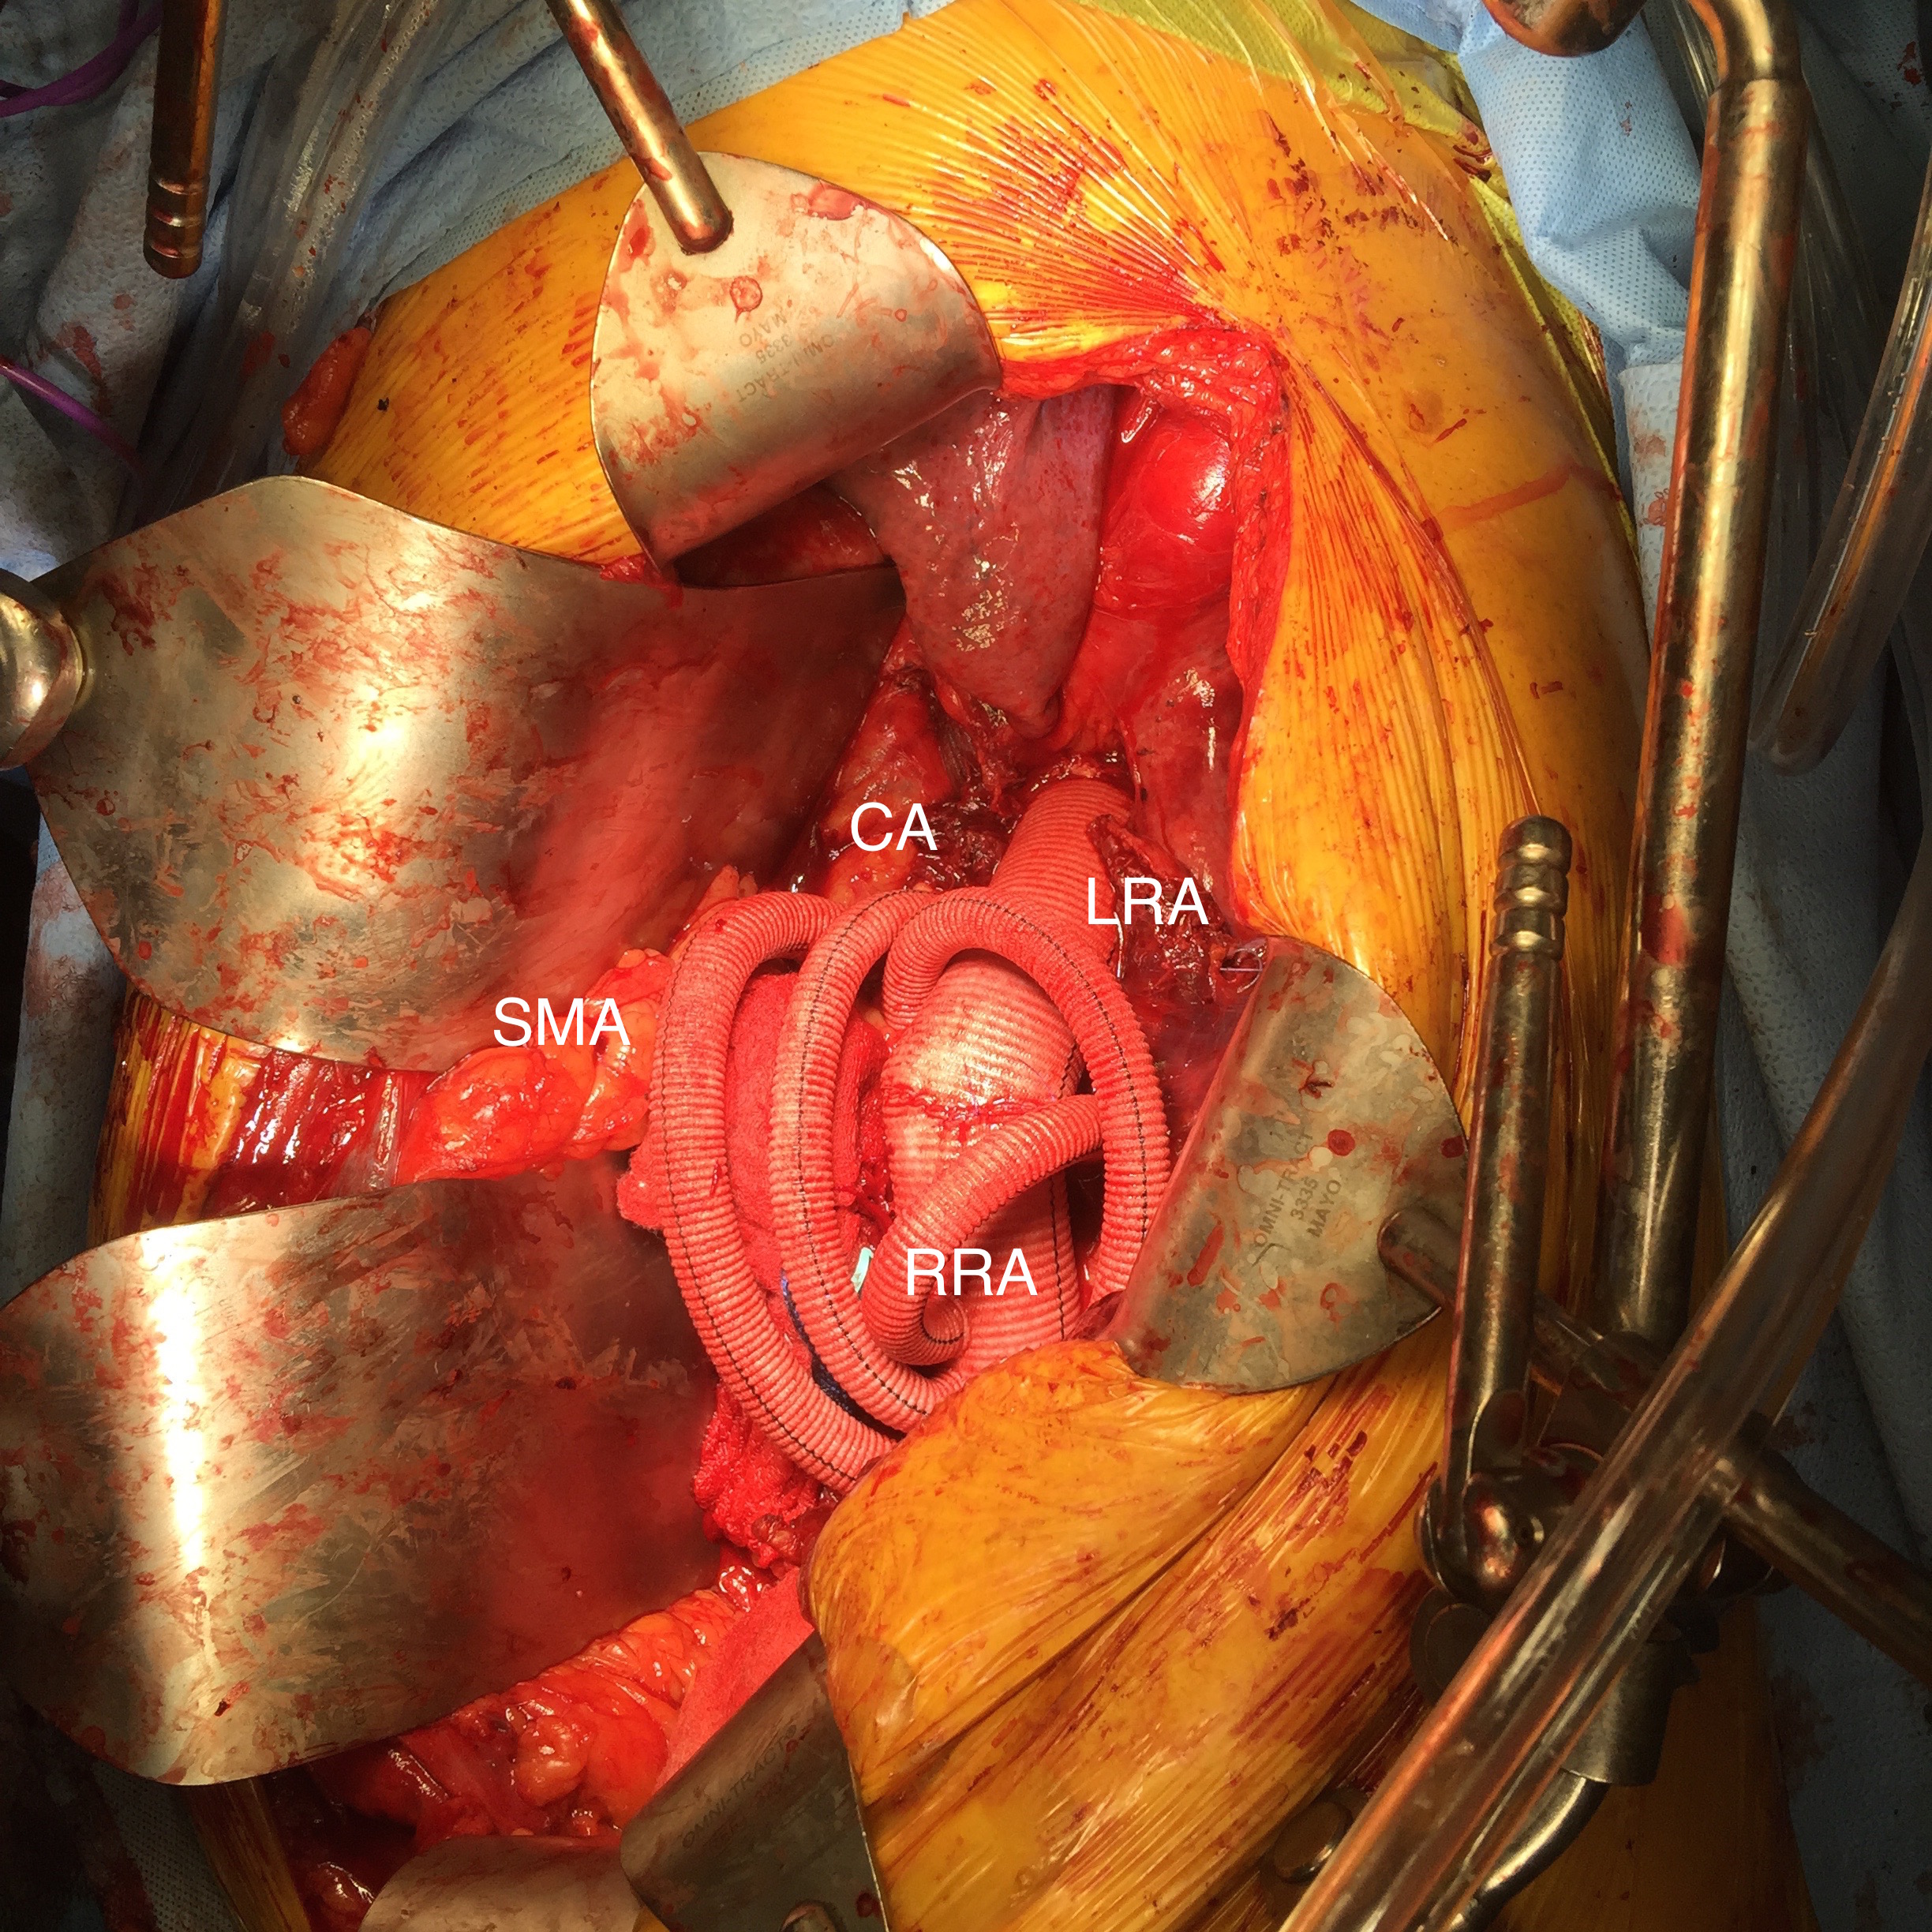

As seen below, the graft excluded the celiac and SMA. Late in the phase of the final aortogram (second panel) there was an endoleak that persisteed despite multiple ballooning. The timing suggested the intercostals and phrenic vessels contributed to a type II endoleak, but it was concerning.

The bypasses were sent from the infrarenal aorta to the common hepatic artery and the SMA close to its origin, and the origins of the celiac axis and SMA were clipped. The bypasses were then done with a 10x8mm bifurcate Dacron graft originally for axillofemoral bypassing. It had spiral rings which I removed at the anastomosis and this resulted in a kink at the closer bypass. Usually, I loop this for iliomesenteric bypass but there was not enough distance from the infrarenal aorta. I have to add a little trick I modified from my pediatric surgery experience as a resident -a Heinecke-Mikulwicz graftoplasty:

This worked to relieve the kink as evidenced on the aortogram above. After closing the laparotomy, I placed a chest tube in the right chest. The patient had a course prolonged by a classic systemic inflammatory response syndrome, with fevers, chills, and leukocytosis. He bled for a while but stopped with correction of his coagulopathy. All blood cultures were negative, but a CT scan was performed out of concern for the endoleak, and the possibility of continued bleeding.